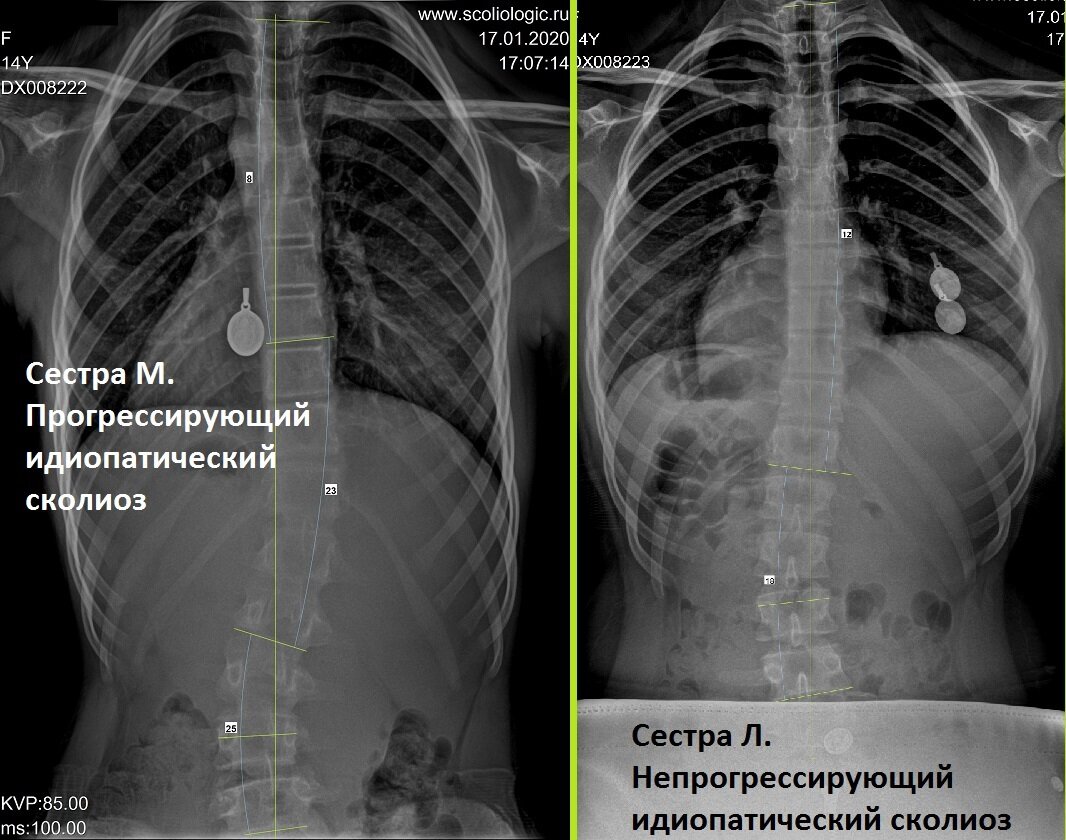

Вот яркий пример: сестры-двойняшки.

Сестры пришли в Сколиолоджик.ру в июне 2019 года. Сестрам по 12 лет.

Слева - сестра М. Первичные градусы - 10-32-25. Корсетное лечение и гимнастика за 7 месяцев привели к результату 8-23-25. Есть над чем работать и к чему стремиться.

Справа - сестра Л. Градусы 12-18. При таких градусах корсет не надеваем, наблюдаем. Но и через полгода градусы такие же. Девочка с сестрой занимается специализированной гимнастикой. Но прогрессии нет и не будет, если ее нет сейчас.